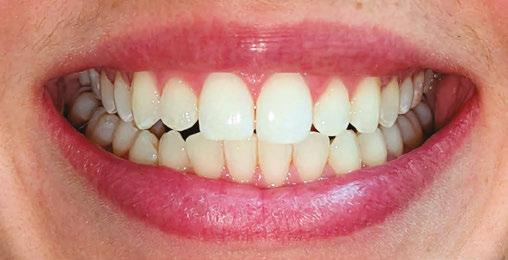

Patient J, a 39-year-old female, (Figures 1, 2, 3, 4, 5, 6) came to the office with concerns about difficulties chewing food and experiencing dry mouth upon waking up in the morning. Additionally, her partner was disturbed by her snoring. Upon examination, several issues came to light:

1. An open bite in the anterior region and a posterior crossbite

2. Breathing through the nose 10% of the time.

3. Lips and cheek muscles actively helping with swallowing food and drinks

4. Lips open 100% of the time

5. Tongue cannot maintain position on a spot, moves between teeth upon swallowing

6. Tongue thrust

7. Weak control over soft palate

Muscle tension around the temporomandibular joint (TMJ) was also evident5 as well as mandibular bilateral lingual torus as response to constant occlusal pressure applied during bruxism.

Figure 2: Anterior view before treatment

Figures 3 and 4: 3. Right side before treatment. 4. Left side before treatment

Figures 5 and 6: 5. Upper arch before treatment. 6. Lower arch before treatment

Figure 12: Anterior view upon the completion of active treatment

Figure 17: Smile upon the completion of active treatment

Figures 13 and 14: 13. Right side upon the completion of active treatment. 14. Left side upon the completion of active treatment

Figures 15 and

15. Occlusal view upon the completion of active treatment. 16. Lower occlusal view upon the completion of active treatment